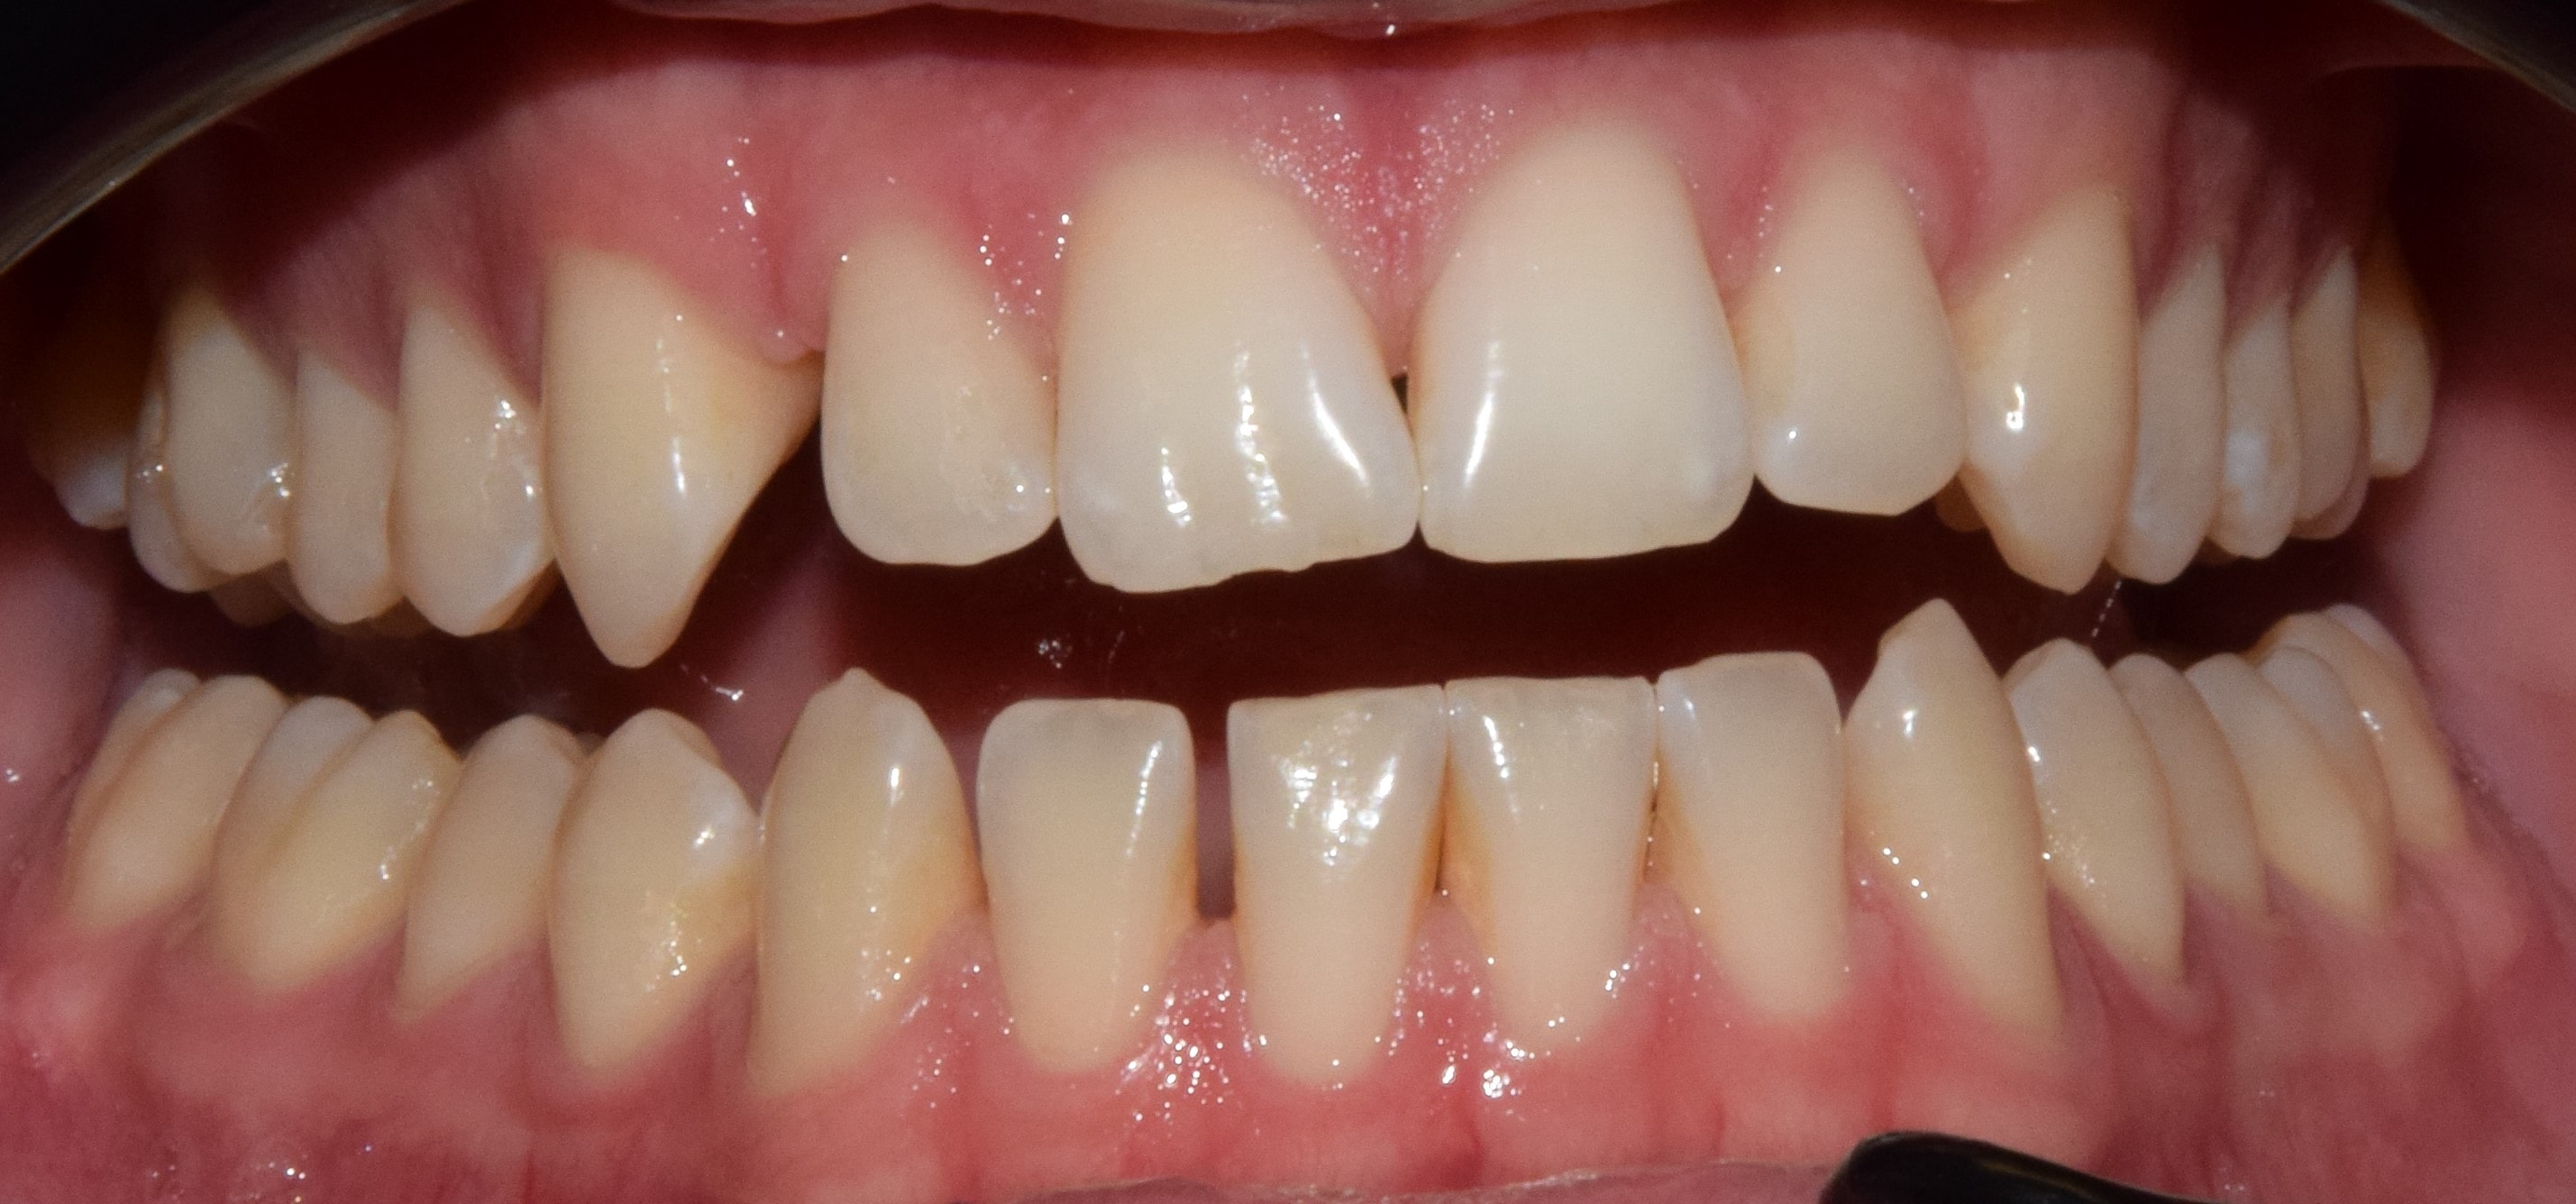

Diasthema medianum

Gyakori fogszabályozási probléma a két felső nagymetsző között jelentkező rés. Ellátását számos faktor befolyásolja. A vegyesfogazatban gyakori, legtöbbször normális jelenség, ami később spontán záródhat, ezért túlságosan korai ellátását semmi sem indokolja. Diasthemat eredményezhet például kifejezett ajakfék, számfeletti fog, kismetsző csírahiány.